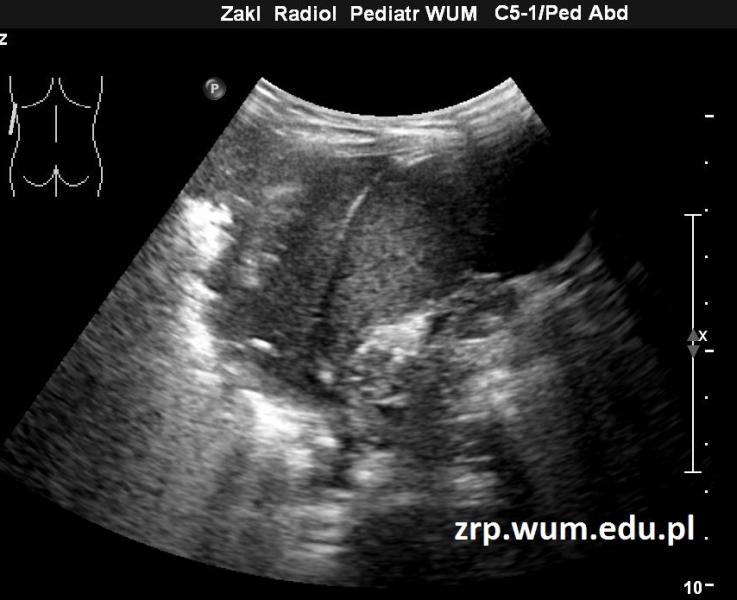

Przypadek 27: 5-letni pacjent zgłosił się do IP z powodu gorączki i bólu brzucha.

Rozpoznanie: W wykonanym badaniu USG jamy brzusznej stwierdzono masywne zmiany zapalne u podstawy płuca lewego, od tyłu; bez płynu w jamie opłucnowej. Czerwona strzałka - duży obszar bezpowietrznego miąższu płucnego u podstawy płuca lewego, żółte strzałki - przepona, biała strzałka - śledziona.